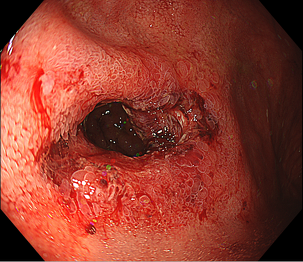

内視鏡下ステント留置術

消化管の狭くなっている部分に対してステント(筒のようなもの)を挿入し狭窄部を広げる治療になります。

主に癌などの悪性腫瘍の狭窄に対して行う治療で、切除不能狭窄の症状緩和目的や腸閉塞症状を伴う狭窄の緊急手術回避目的で行います。